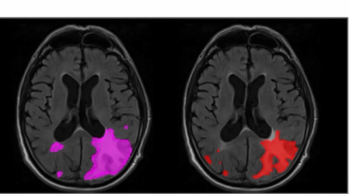

Through AI technology, Neurophet AQUA now provides multiple sclerosis (MS) analysis with a combination of lesion quantification and enhanced segmentation of T2-FLAIR MRI.